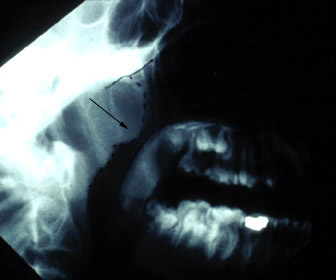

Lateral neck film shows hypertrophic adenoids.